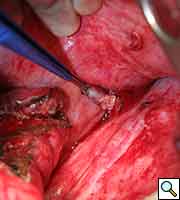

![]() |

| Figure 1: Initial chest radiograph |

A previously healthy 43-year-old male presented with cough, fevers, and leukocytosis. A chest radiograph (Figure 1) revealed extensive consolidation in the right lower lung containing multiple cavities with air-fluid levels consistent with a necrotizing infection. A chest computed tomogram (Figure 2) showed an abscess cavity and consolidation in the right lower lobe with an aberrant blood supply from the descending aorta. This systemic blood supply was confirmed by subsequent 3D reconstruction (Figure 3). He was initially treated with IV antibiotics, resulting in normalization of his temperature and white blood cell count. He was then discharged home on a 3-week course of oral antibiotics. Three days prior to a planned surgical resection, he underwent angiographic localization of the feeding artery (Figure 4) and coil embolization (Figure 5).